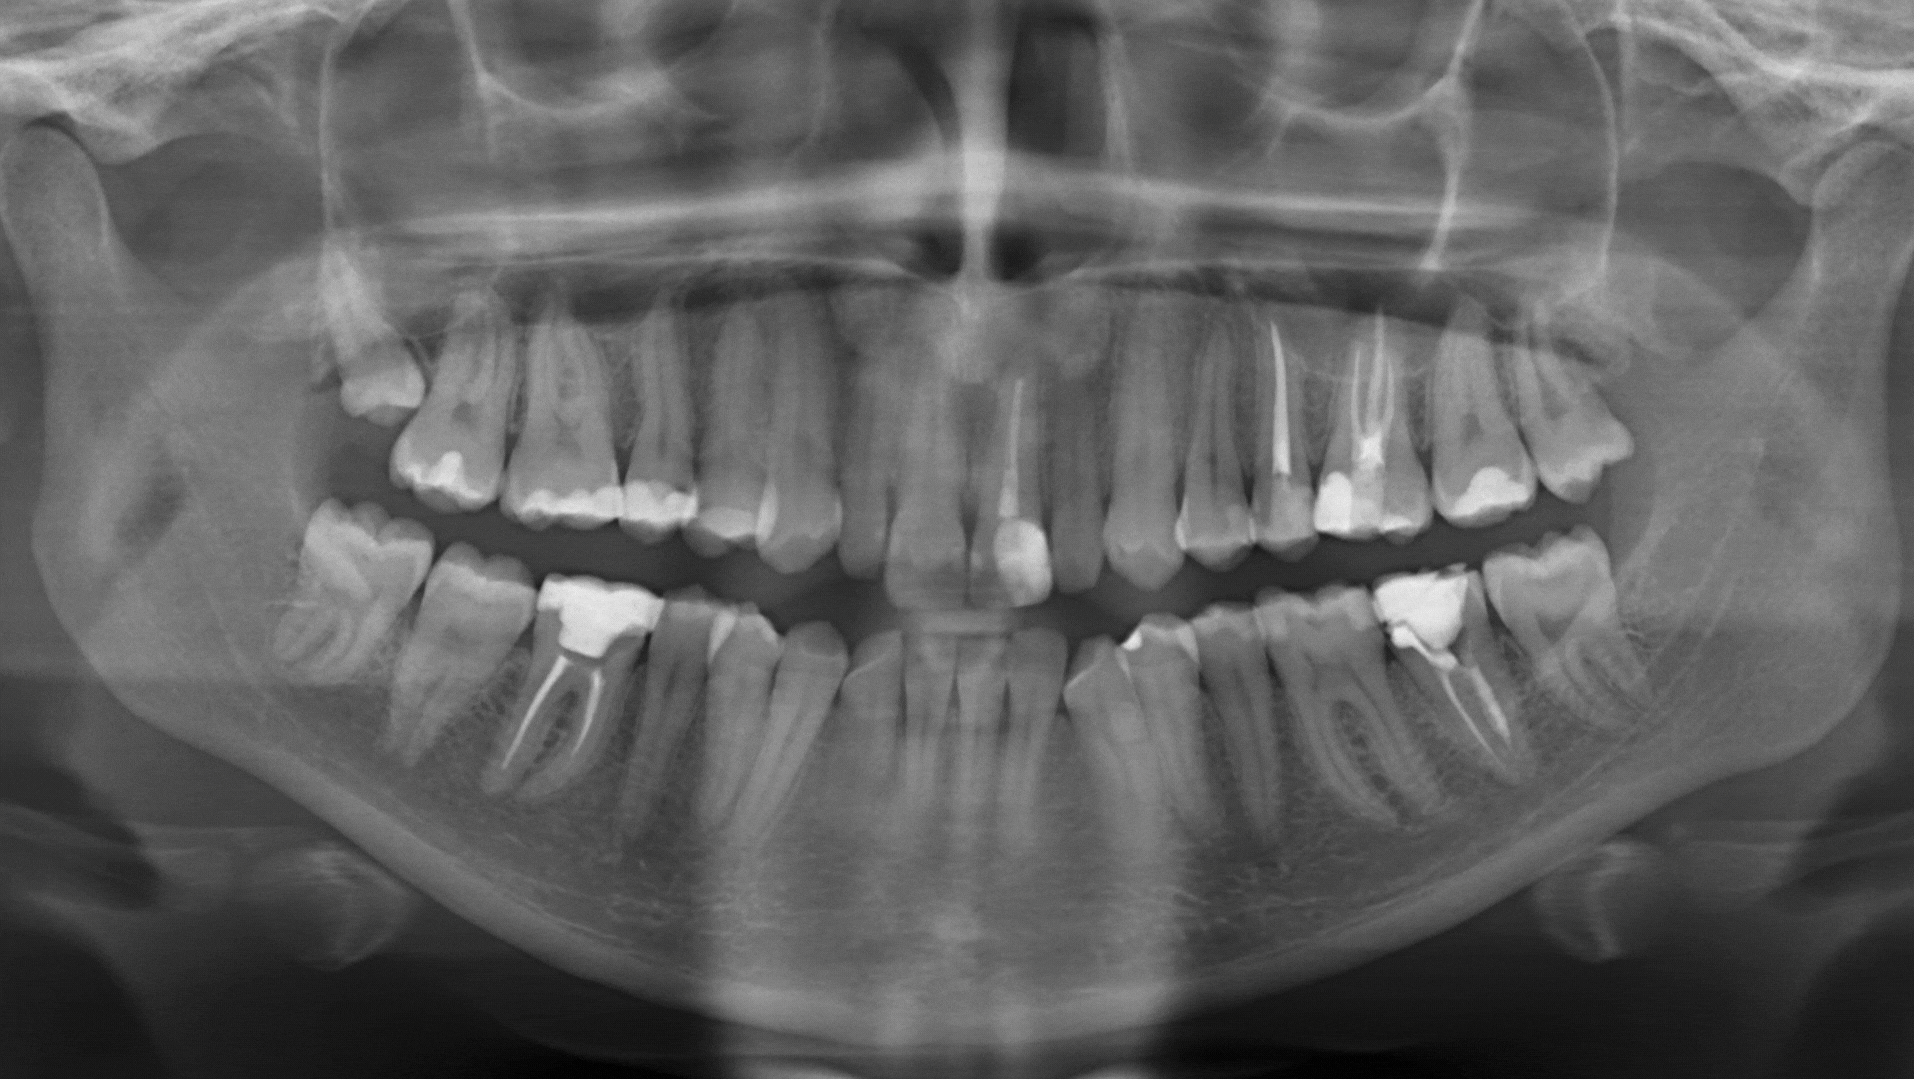

Advanced intelligence for accurate panoramic X-ray analysis and confident clinical decision-making

Our AI models are trained on a rigorously curated dataset of high resolution, clinically annotated dental radiographs enabling reliable diagnostic performance for pathology detection.

AI systems designed to detect dental pathology and anatomical features with clinical accuracy and reliability

Our computer vision systems identify and evaluate the widest range of pathologic and restorative features detectable in radiographic and 3D dental imagery.Our computer vision systems identify and evaluate the widest range of pathologic and restorative features detectable in radiographic and 3D dental imagery.Our computer vision systems identify and evaluate the widest range of pathologic and restorative features detectable in radiographic and 3Ddental imagery.Our computer vision systems identify and evaluate the widest range of pathologic and restora